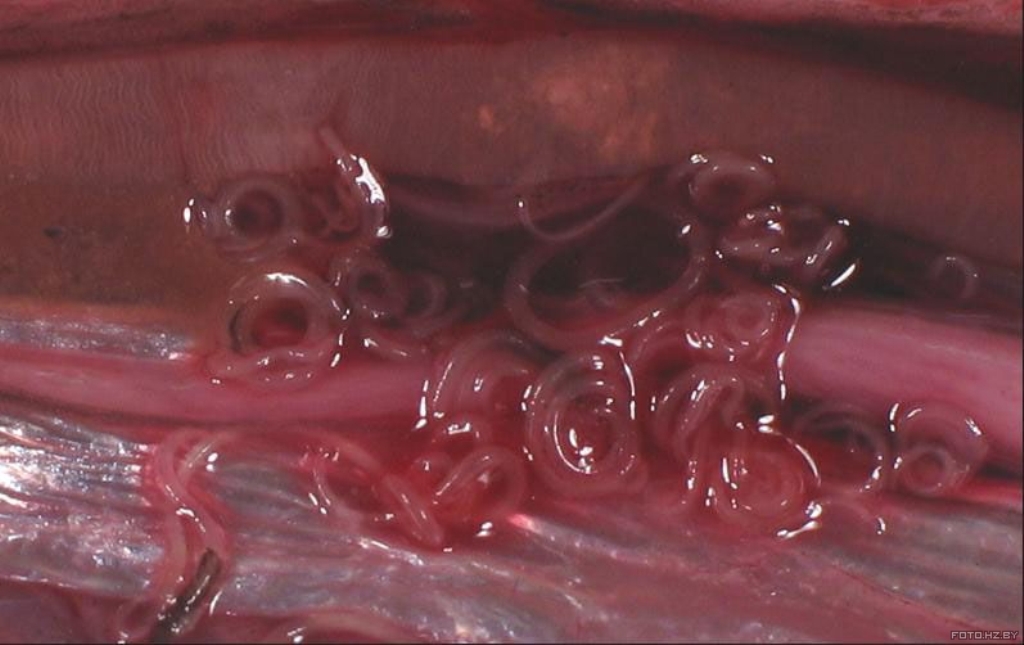

Анизакиоз

Анизакиоз. Возбудители анизакидоза человека — личиночные стадии развития гельминтов родов: Anisakis, Contracaecum, Pseudoterranova, Hysterothylacium, относящихся к отряду Ascaridida Skrjabin et Schikhobalova, семейству Anisakidae Skrjabin et Korokhin. Окончательными хозяевами этих гельминтов служат многие морские млекопитающие (китообразные, ластоногие), хищные морские рыбы и рыбоядные птицы, в желудочно-кишечном тракте которых паразитируют самцы и самки анизакид. Средняя длина самок 60-65 мм, самцов — 50-55 мм. Тело веретенообразное, суженное к обоим концам (более сужено к головному концу). На головном конце имеется три губы. В теле рыбы находятся чаще в состоянии «плоской свёрнутой спирали». Могут находиться как в полостях тела так и в мышечной ткани.

image

Личинки круглых червей могут поражать почти все виды морских рыб: тресковые, окунёвые, лососёвые и др. В частности, поражённость сельдевых в Балтийском море — 30%, а в Северном море — 55–100%. Рискуют заболеть все, кто любит японские блюда, приготовленные из сырой рыбы. Личинки анизакид могут провоцировать развитие язвы кишечника, инкубационный период — от 4–6 часов до 7 дней.

Клиническая картина заболевания обусловлена местом локализации паразитов. При нахождении личинок в просвете кишечника симптоматика может быть весьма скудной. При желудочной локализации (наиболее частая форма заболевания) больных беспокоит сильная боль в эпигастрии, тошнота, рвота, иногда с кровью. Отмечается субфебрильная или фебрильная лихорадка, развитие аллергических реакций немедленного типа (крапивница, отек Квинке).

В случае ретроградной миграции личинок анизакид из желудка в пищевод возникают боль и раздражение в горле, кашель. При кишечном анизакидозе больные жалуются на боли в области пупка и в правой подвздошной области, урчание в животе, метеоризм. Возможно возникновение симптомокомплекса острого живота, характерного для аппендицита или непроходимости кишечника.

К серьезным осложнениям кишечного анизакидоза относится прободение кишечной стенки и попадание кишечного содержимого в брюшную полость с развитием перитонита.